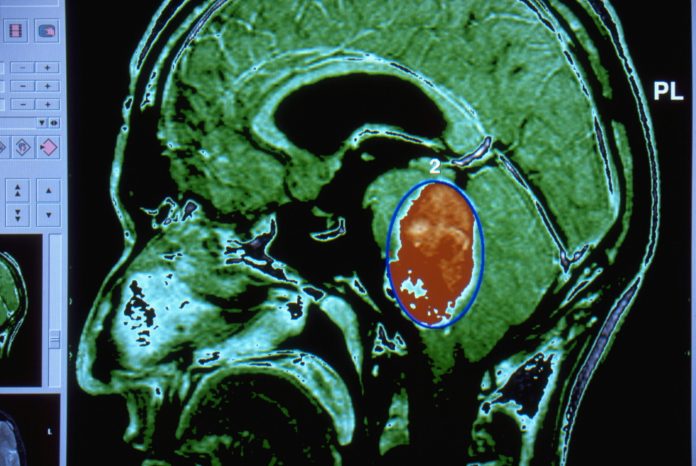

Ependimoamele sunt tumori care se dezvoltă în creier sau măduva spinării și reprezintă al treilea cel mai comun tip de tumoră cerebrală la copii. Acestea afectează aproximativ 250 de copii în Statele Unite anual, fiind cel mai frecvent diagnosticate la copii cu vârsta de opt ani sau mai mici. Tratamentele principale pentru aceste tumori includ îndepărtarea chirurgicală a tumorii, urmată de radioterapie și chimioterapie, deși chimioterapia nu a demonstrat o eficacitate constantă. În prezent, nu există terapii țintite sau studii clinice care să vizeze ependimomele conduse de ZFTA.